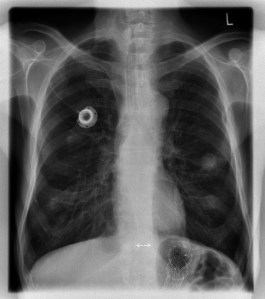

A nurse comes in, closes the curtain, and accesses my Medi-port. A Medi-port is a completely implanted device that consists of the following: Reservoir – a hollow titanium disk that has a rubber septum. The reservoir is implanted in a pocket just below the skin on the chest wall. In my case, the upper left hand side, right below my collar bone. Catheter – a tube that is connected to the reservoir and placed into one of the large veins of the chest. In my case, into the heart. The nurse feels for the reservoir and accesses it with a large needle. Now ports are supposed to be good for two way flow (drawing blood and administering medication), however, my port is finicky. Occasionally, the nurses are able to draw blood, using a number of techniques such as having me lie flat, turn my head to the right, and cough. The nurses have also tried flushing the port with saline, heparin (a blood thinner), to no avail. Basically my port is a bitch and only allows nurses to draw blood from it sometimes, which means the nurses have to draw blood from a vein in my left arm. (My right arm can’t be used for blood draws, blood pressure readings, acupuncture, etc. I had the lymph nodes removed under the right armpit. Any injury to the right arm can cause lymphedema, which is a swelling of the arm). It’s a real pain that my port doesn’t work like it is supposed to because instead of being stuck with a needle once, I have to be stuck twice, every week!